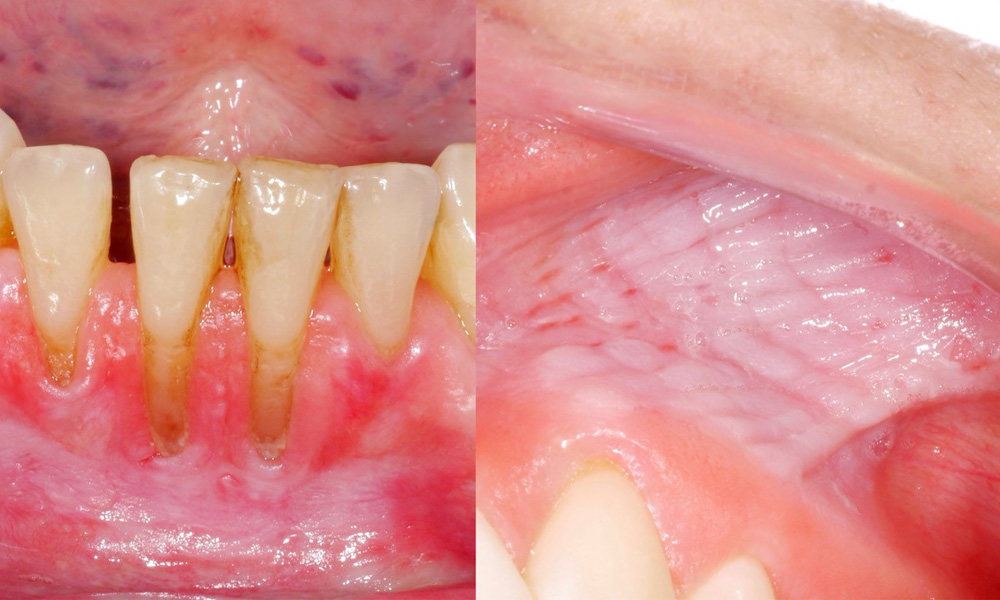

The clinical examination showed that regular consumption of snus can have the following effects on the oral mucosa:

• Approximately 80% of those examined who consumed snus daily had snus-induced mucosal lesions.

• Approximately 20% of those examined who consumed snus daily had snus-induced gingival recession.